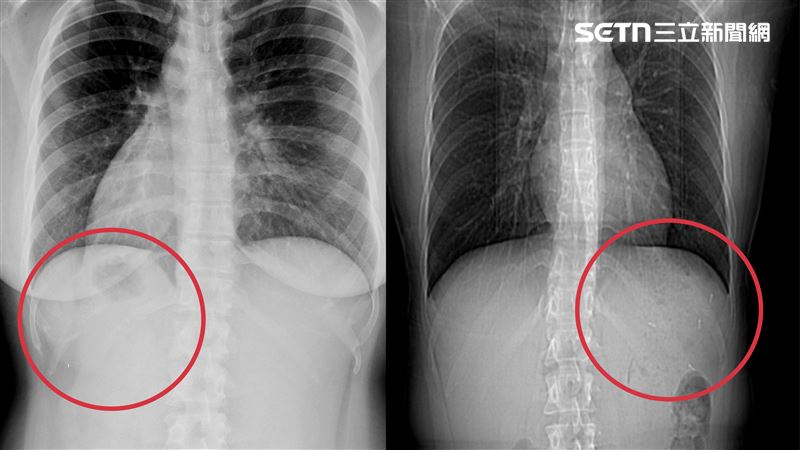

劉家嘉醫師表示,二寶媽是先天性臟器逆位患者,全身臟器位置與常人相反,發生率僅萬分之一,手術困難度極高。(圖/翻攝畫面)

新悅美型醫學診所體重管理中心院長劉家嘉醫師表示,這名二寶媽在高中時因嚴重脹氣就醫,發現先天性臟器逆位,此症狀發生率僅萬分之一,患者體內的心臟、肝臟、胃腸位置與常人完全相反,醫療診治相對困難。為了降低風險,二寶媽盡可能避免動手術,二寶也都是自然產。

二寶媽是先天性臟器逆位患者,全身臟器位置與常人相反,發生率僅萬分之一,手術困難度極高。(圖/翻攝畫面)

劉家嘉醫師表示,這類手術最大的挑戰在於「空間重構」。醫師需在腦中即時轉換鏡像操作邏輯,克服長年累積的操作慣性,精確判斷每一針縫合的位點。這台手術也是目前全球第二例臟器逆位ESG手術,讓台灣高階內視鏡減重技術再度獲得國際矚目。